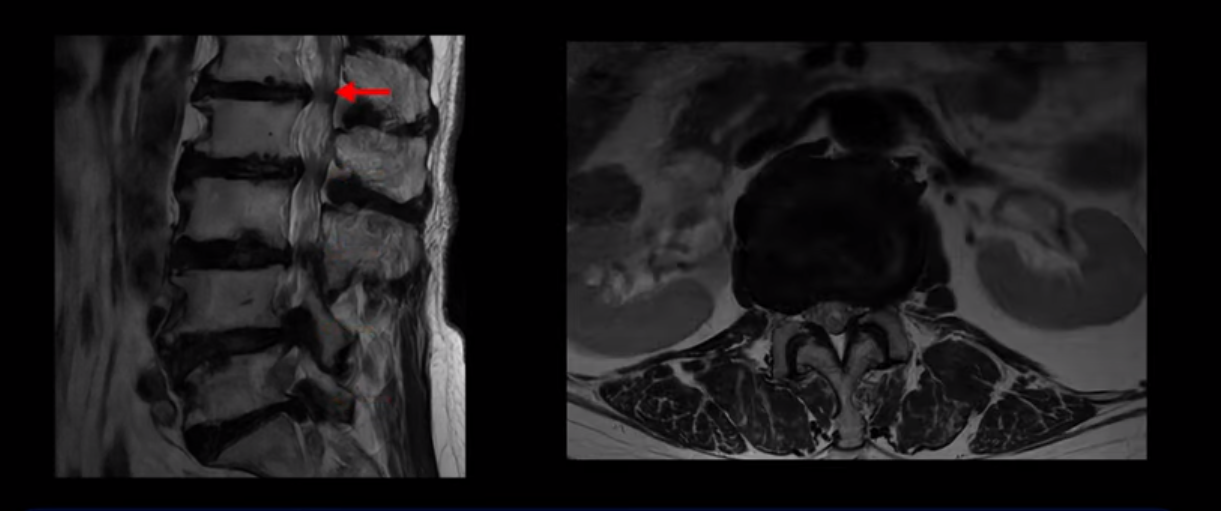

이 환자분은 MRI로 보면 허리 여러 마디가 신경이 매우 심하게 눌려 보이는 분입니다. 이분 MRI를 보면서 간단히 설명해 드린 후 어떻게 이렇게 신경이 심하게 눌린 환자분이 수술 없이 근육신경재활치료로 좋아질 수 있는지, 다리가 아파 걷지 못하는 환자가 어떻게 안 아프고 잘 걸을 수 있게 되는지, 10년 동안 괴로웠던 양 발의 시린 증상은 어떻게 사라질 수 있는지, 치료는 어떻게 하는지 자세히 설명 드리겠습니다.

MRI 보시면 (2-8) 허리의 5마디가 전부 다 심하게 퇴행되어 있습니다.

5마디 전부 다 심한 중심성 협착이 있습니다.

1번 2번,

2번 3번,

이렇게 모두 다 심하게 막히는 경우는 드문데요. 또한 오른쪽, 왼쪽 신경이 빠져나가는 추간공도 다 심하게 막혀있습니다.

오른쪽, 왼쪽 이렇게 신경 구멍들이 다 좁아지고 신경이 눌리니까 양쪽 다리가 발바닥까지 아파서 걷기 어렵고 양쪽 발이 10년 넘게 시린 겁니다. 당연히 수술해서 눌린 신경을 풀어줘야 한다고 들으셨는데요. 이런 환자분을 어떻게 수술 없이 치료할까요? 지금부터 설명해 드립니다.

이분 신경이 눌리는 증상은 오래됐지만, 증상이 아주 심해진 건 올해 들어와서입니다. 그럼, 이분 MRI 영상도 이렇게 심하게 안 좋아진 게 올해 들어와서일까요? 이분의 MRI로 보이는 협착은 아주 오래된 겁니다. 그래서 신경 구멍이 심하게 좁아진 것도 올해가 아니고 오래된 겁니다. 작년, 재작년에 훨씬 덜 아팠을 때 MRI를 찍었어도 신경 구멍 좁은 정도는 별반 차이가 없었을 겁니다.